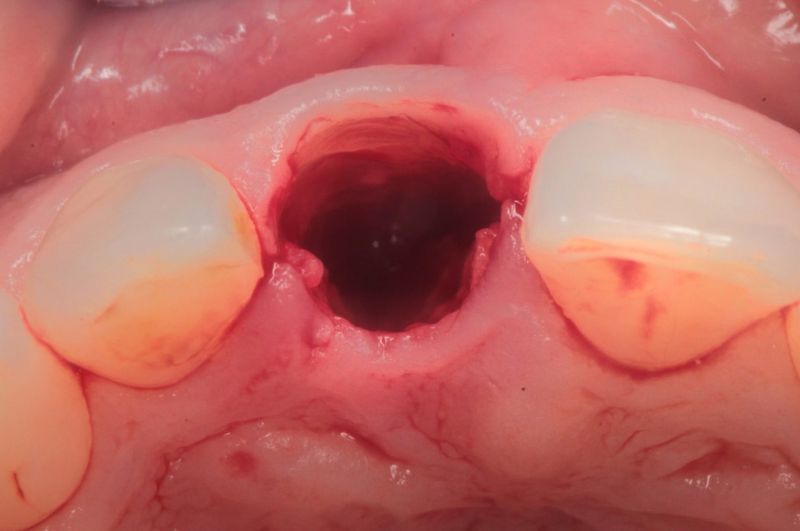

Implantacje natychmiastowe to zabiegi wszczepiania implantów bezpośrednio bo zabiegu ekstrakcji zęba. Umożliwiają wprowadzenie implantu w miejsce po usunięciu zęba podczas jednej wizyty. Bardzo często implantacja natychmiastowa nie wymaga dodatkowego cięcia, gdyż wykorzystywana jest luka w wyrostku zębodołowym powstała po wyrwaniu zęba.

Jeżeli lekarz nie widzi żadnych przeciwwskazań ogólnoustrojowych oraz istnieją dobre warunki podłoża kostnego, można od razu po ekstrakcji przeprowadzić zabieg implantacji. Warunkiem wykonania natychmiastowego wszczepienia implantu jest odpowiednia jakość i wielkość wyrostka zębodołowego.

Natychmiastowe wszczepienie implantu hamuje zanik kości, procesy zachodzące po utracie zębów, ale również zapewnia komfort ze względów estetycznych i praktycznych.